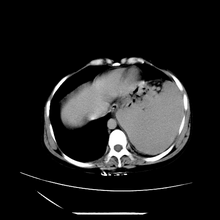

女性,41岁,发现左腹部包块3年,现行ct检查,检查前做过静脉肾盂造影。

左侧低密度区是脂肪密度,中间可见条索状软组织样密度影,现主要想知道左肾前下缘圆形软组织样密度影,内见低密度水样密度影,这是什么?

脾脏增大,左肾后方脂肪增多,脊柱前方脂肪增多,左肾窦脂肪增多,左肾变形,双肾积水以左侧为著,左肾内侧及上方见环形软组织肿物影,内部低密度区,考虑1盆腹腔/腹膜后及左肾窦脂肪增多症2左肾内侧病灶可能为左肾上腺病灶,可能为脂肪增多的原凶

1)考虑左肾替代性脂肪瘤病;不排除左肾错构瘤。2)双肾积水。

肾窦脂肪瘤病及肾替代性脂肪瘤病被认为是脂肪增殖程度不同的一种疾病。正常情况下肾窦内有少量脂肪组织充填,在某种情况下肾实质会发生萎缩,而以肾窦、肾门为中心脂肪或(和)纤维组织可出现增殖,当增殖局限在肾窦、肾门区时称为肾窦脂肪瘤,若同时部分或全部取代了萎缩破坏的肾实质时称为肾替代性脂肪瘤病。

ct典型表现为以肾窦肾门为中心大量弥漫性脂肪积聚,鹿角状结石及萎缩的肾实质。合并肾周感染时,肾轮廓不清,周围有粘连性改变。

左肾周脂肪堆积征【原因?】,双肾逆行造影术后;脾大【原因?】